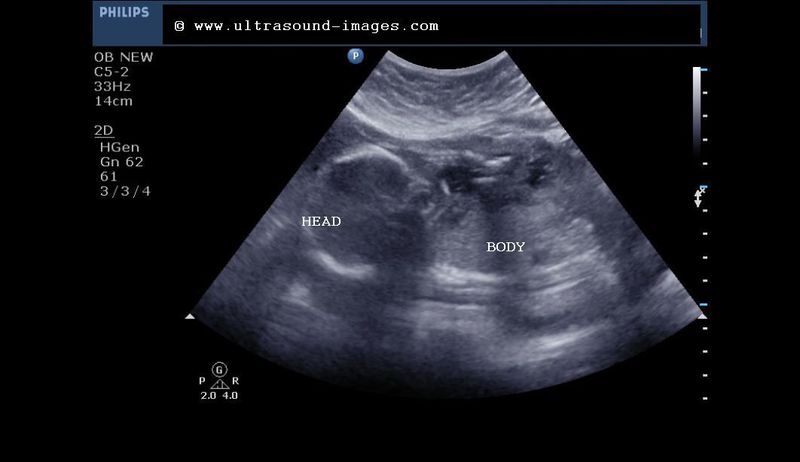

Severe oligohydramnios in late 2nd trimester

This is the case of a 19 week fetus with severe oligohydramnios. Fetus lies in breech presentation. The ultrasound images below show lack of any fluid pocket or very little amniotic fluid in any of the pockets.this patient had bleeding PV with a possible premature rupture of the amniotic membrane

Lack of fluid ( liqor amni) even around the Fetal abdomen or the Fetal limbs

Very little or total absence of amniotic fluid can result in very poor imaging quality

Among the Causes of oligohydramnios are- premature rupture of membranes, Fetal hypoxaemia, renal agenesis or dysgenesis, intake of certain drugs, Fetal demise and also Fetal IUGR. oligohydramnios is diagnosed when the four quadrant AFI or amniotic fluid index is less than five or the maximum vertical fluid pocket is less than 2 cm. Among the complications of such severe oligohydramnios are Fetal limb contractures and Fetal lung hypoplasia.